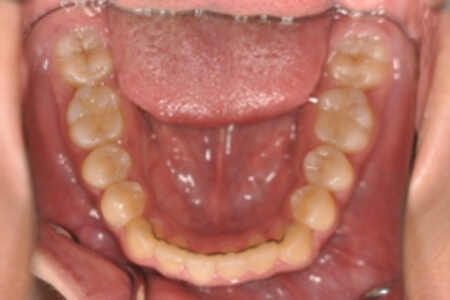

動的治療終了時

症例 症例 症例 症例 症例